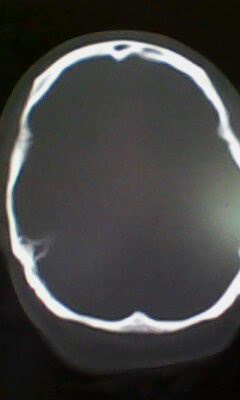

标题: CT25171:患者间断性头痛 无外伤史 [打印本页]

标题: CT25171:患者间断性头痛 无外伤史

右侧额叶脑穿通畸形囊肿。

右侧额叶脑穿通畸形囊肿。支持!